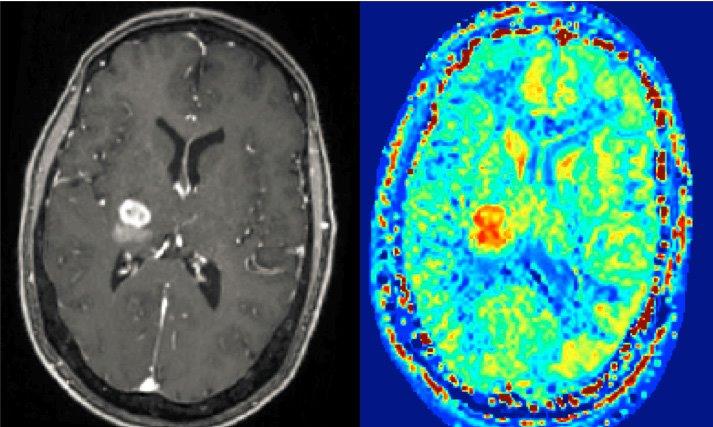

Mit Hilfe der Magnetresonanztomografie (MRT) lassen sich in der heutigen Medizin vor allem die Weichteile im menschlichen Körper sehr gut darstellen – und helfen in der Diagnostik, Veränderungen wie Tumoren zu erkennen. Viele Erkrankungen lösen allerdings bereits Veränderungen im Zellstoffwechsel aus, bevor im MRT tatsächlich eine substanzielle Strukturveränderung des Gewebes zu erkennen ist. Ein Forschungsteam der Friedrich-Alexander-Universität Erlangen-Nürnberg (FAU) um Prof. Dr. Moritz Zaiß, Professur für Multimodale Bildgebung in der klinischen Forschung, und der Technischen Universität Graz arbeitet jetzt an einem Verfahren, um bereits diese Stoffwechseländerungen im MRT sichtbar zu machen und so einen wichtigen Beitrag für die Früherkennung von Krankheiten durch MR-Biomarker zu leisten. Das Projekt wird von der Deutschen Forschungsgemeinschaft und dem österreichischen Fonds zur Förderung wissenschaftlicher Forschung mit 650.000 Euro gefördert.

Grundsätzlich könnte die Magnetresonanztomografie dies leisten, gerade die neuen leistungsstarken Hochfeld-Magnetresonanztomografen mit Feldstärken von sieben Tesla oder mehr. In verschiedenen Molekülen nämlich, die in der zellulären Struktur oder im Zellstoffwechsel vorkommen – etwa Proteine und Stoffwechselzwischenprodukte, so genannte Metaboliten – sind ebenfalls Wasserstoffatome enthalten sind, allerdings in deutlich geringerer Konzentration als in Wasser selbst. Ein Lösungsansatz ist das so genannte CEST-MRT: Die Abkürzung CEST steht für den „chemical exchange saturation transfer“, ein Verfahren, das sich den chemischen Prozess des Protonenaustauschs zu Nutze macht, um die Sensitivität des MRT so zu erhöhen, dass es auch auf die geringen Konzentrationen von Wasserstoffprotonen in Proteinen und Metaboliten anspringt. Das interessante an der CEST-MRT-Methode ist, dass sie nicht-invasiv ist und keine Kontrastmittel benötigt.